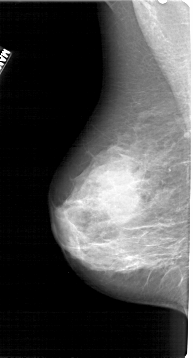

A_1270_1.LEFT_MLO

LEFT_MLO LINES 5356 PIXELS_PER_LINE 2881 BITS_PER_PIXEL 12 RESOLUTION 43.5 NON_OVERLAY